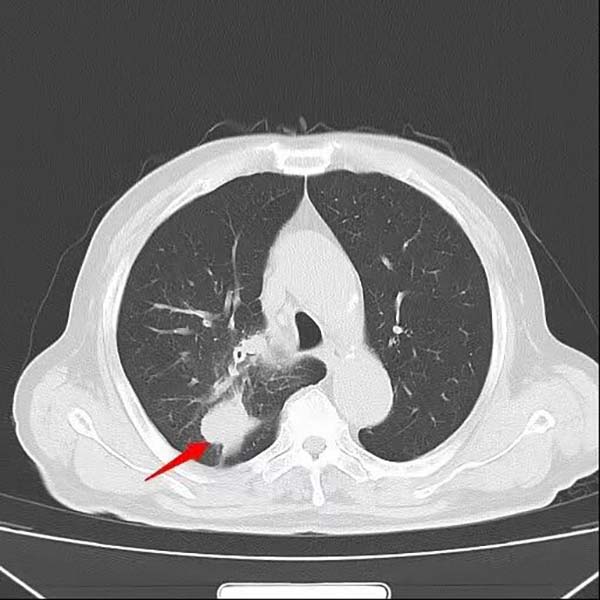

入院后,胸外科团队为患者行超声引导下经支气管针吸活检(EBUS-TBNA),病理结果提示为小细胞癌,并发现纵隔淋巴结转移。进一步全身检查显示,患者已出现肋骨及肝内多发转移,诊断为右肺上叶小细胞肺癌(cT3N2M1c IVB期)。